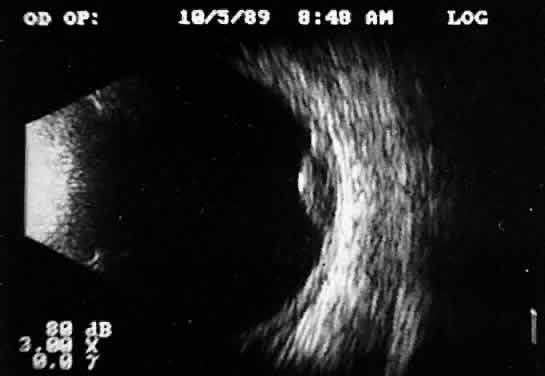

POSTERIOR VITREORETINAL INTERFACE EVALUATION

Recent improvements in image quality and fused, real-time display have made ultrasound image interpretation easier for every ultrasonographer. Visualization of subtle changes such as movement and recognition of the posterior formed vitreous hyaloid are now possible, even in clear media situations. These clear vitreous structures, which are often exceedingly difficult to appreciate optically, can be recognized ultrasonically after a relatively short period of training (Fig. 17). Clinically, establishing the position of the posterior hyaloid is important in evaluating a variety of vitreous retinal disorders, such as macular holes, tractional detachments, and partial or complete vitreous separations.16,17

Fig. 17. Contact B-scan: posterior formed vitreous face separation, with prominent Weiss ring evident.